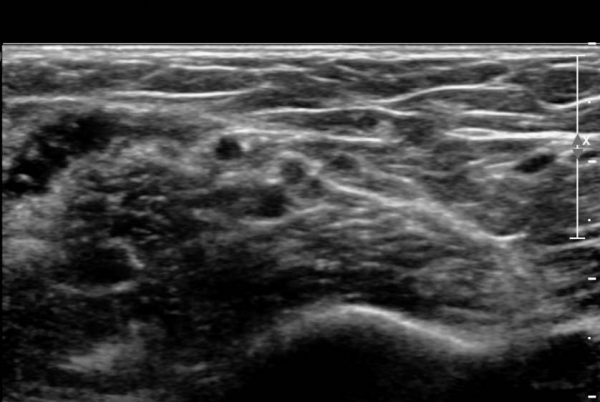

Á¤Á߽Űæ Á¾´Ü¸é °Ë»ç¿¡¼­µµ  Á¤Áß ½Å°æ ÀϺΠ´Ù¹ßÀÇ ¹æÃßÇü Àú¿¡Ä¿ ºÎÁ¾ÀÌ °üÂûµÈ´Ù(»çÁø 6, 7).